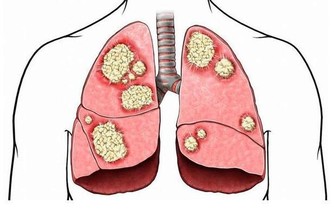

(圖片來源image.baidu.) 近幾年,肝癌的發病率越來越高,並成為嚴重威脅人類健康的一大殺手,一般情況下,肝癌的發生跟日常飲食脫不了關係,

因為食物發霉之後,微生物代謝會產生一種毒性非常大的強致癌物質--黃麴黴毒素,

它是一種毒性極強的物質,進入人體以後主要對人的肝臟組織進行破壞。

作為人體的排毒器官,肝臟負責將人體的有毒物質分解轉化,當毒素多到肝臟無法分解的時候,就會留在肝臟中,

肝臟中堆積太多的有毒物質勢必會傷害肝細胞,時間久了,肝細胞就會死亡。